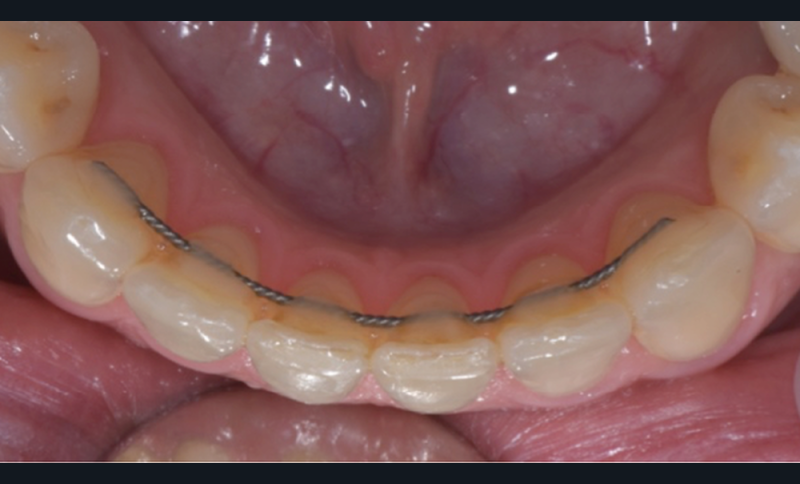

Dans le premier cas, il s’agit de plaques de nickel-titane usinées (fig. 10a-b) ou de fils de contention, pliés par un robot. Dans le deuxième cas, il s’agit de gouttières thermoformées sur des modèles (fig. 11), modifiés ou non, voire bientôt des gouttières imprimées directement.

Le début et milieu d’après-midi seront consacrés à l’empreinte numérique, désormais utilisée pour les empreintes d’étude, les set-up, le thermoformage. Les Drs Guillaume Lecocq et Stéphane Desplanques monteront le thermoformage et comment ces empreintes numériques peuvent permettre de confectionner des appareils vestibulaires, linguaux, voire des aligneurs (fig. 1 et 2).